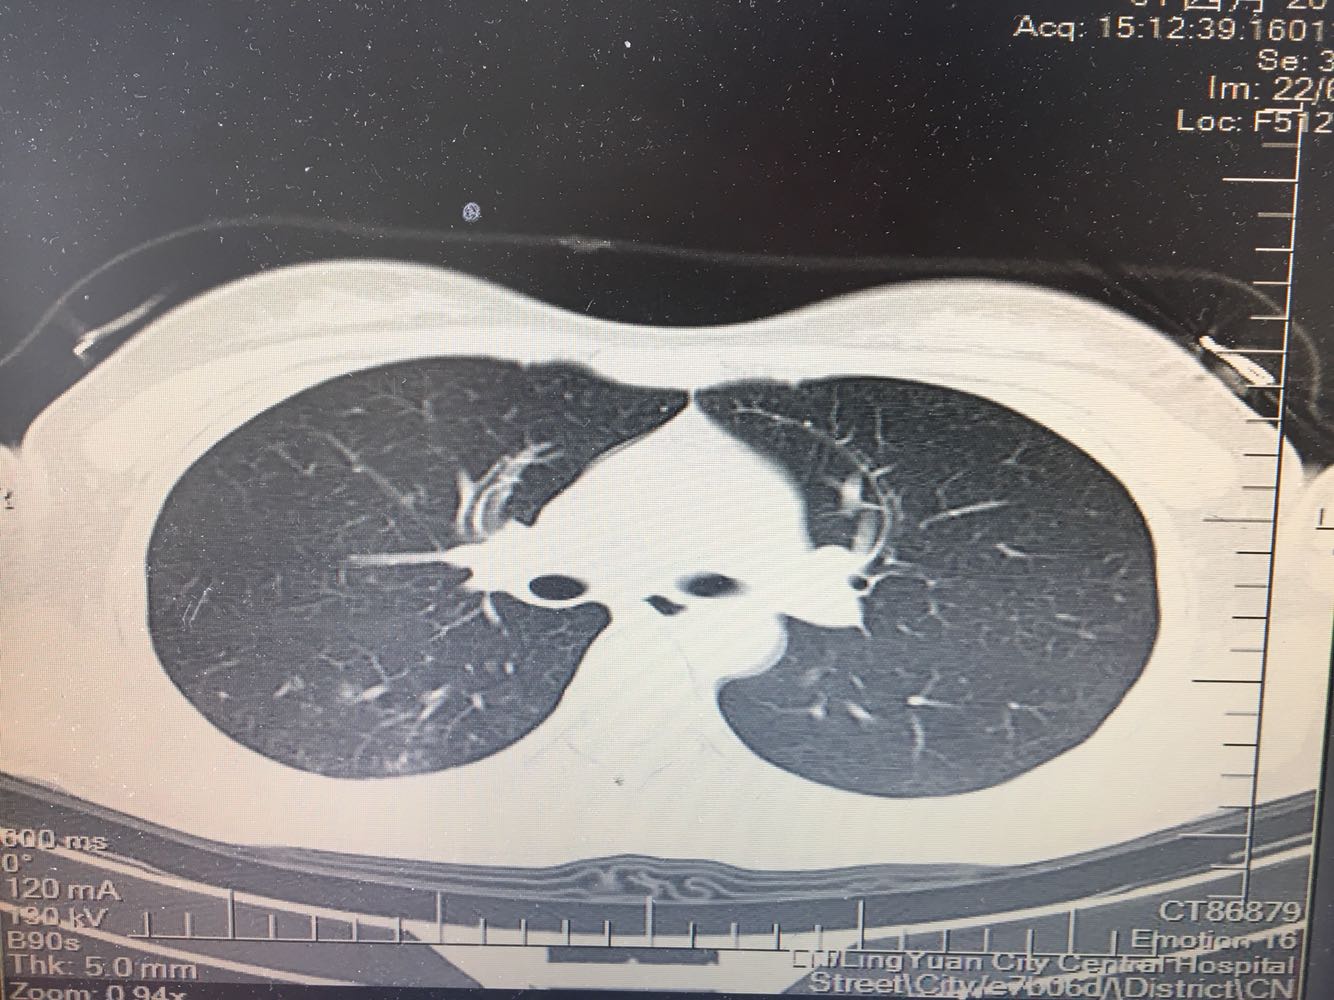

女,26岁,咳嗽1周,咳痰不畅,咽喉痒,口服阿莫西林无好转,昨日发热,体温38.5摄氏度,于门诊查肺CT后以肺炎收入院,病来无盗汗,无咳血,无消瘦及乏力,无头痛,无肢体酸痛,饮食睡眠可,二便正常

神清言明,咽部无充血,扁桃体不大,双肺呼吸音清,无罗音,服软无压痛。

支原体肺炎?肺结核?

支原体抗体1:160,结核抗体弱阳性。支原体肺炎个别可见上叶病变,该患无结核中毒症状,考虑支原体肺炎可能性大,但肺尖为结核好发部位,需要抗炎治疗后复查观察疗效。